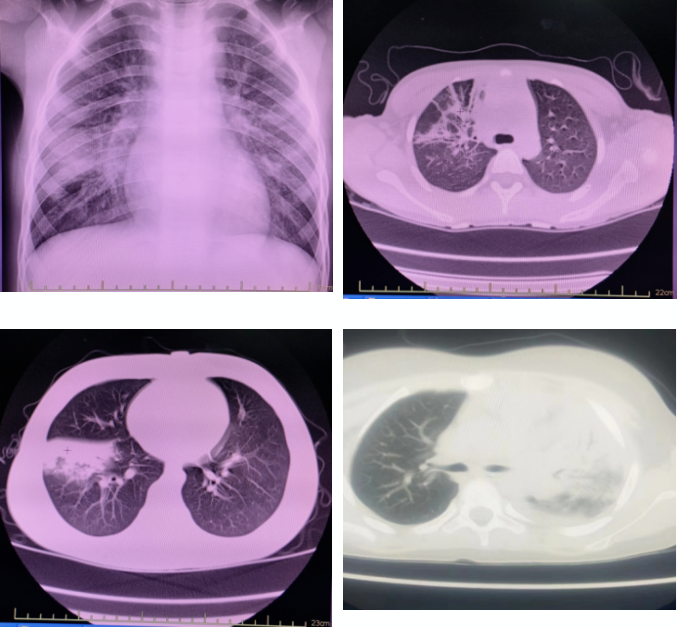

影像学检查

影像学表现是临床判断病情严重程度和评估预后的主要依据之一。肺炎支原体肺炎早期胸片或胸部CT主要表现为支气管血管周围纹理增粗、支气管壁增厚等。肺泡炎性改变可有磨玻璃样阴影、斑片状、节段乃至大叶性实变,常见肺不张,重者可合并胸腔积液。